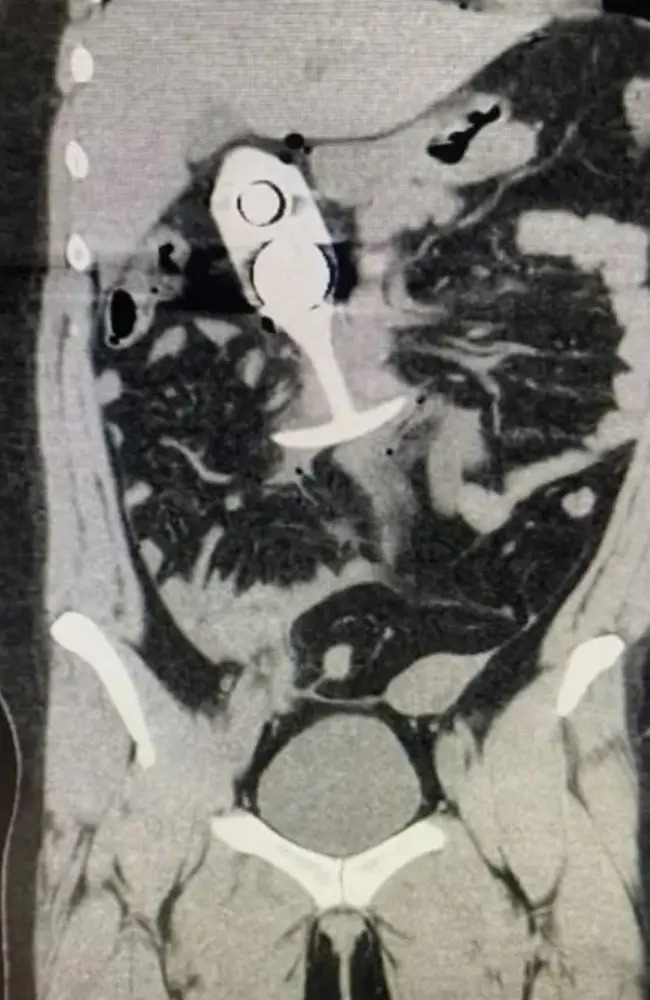

美國一名23歲女子在接受磁力共振掃描時,竟因體內一件她相信是100%硅膠的“性玩具”,導致她遭受嚴重創傷。

磁力共振(MRI)掃描使用強力磁鐵和無線電波來創建身體內部的高度詳細影像,因此在進行掃描前,須從身體上取走所有金屬物體。然而,涉事女子在接受MRI檢查時,肛門內插入了一個硅膠塞,并沒有取出來。這個匿名女子并不知道,她本以為身上那件是100%硅膠的性玩具,其核心實際上含有金屬。

一份向美國食品及藥品管理局(FDA)提交的報告稱,事件導致該個成人性玩具“穿過她的身體”,導致患者“痛苦尖叫”。

雖然這宗事件發生在2023年4月,但據稱顯示患者事發后掃描的圖像,最近開始在網上流傳,提示人們不要在掃描期間佩戴任何金屬物品。

肛塞穿過女子身體,致她身受重傷。 路透社

▲肛塞穿過女子身體,致她身受重傷。 路透社

有關內容進一步聲稱,塞子以“聲速”從患者的直腸被拉到胸腔,受創者幸存下來,但傷勢嚴重。

還有官方報告證實,該女子使用磁力共振掃描設備時發生了“不良事件”,“患者接受了篩檢,但并未透露自己插入了肛塞”。

報告并說,檢查結束、技術員把檢查臺拉出來時,病人開始尖叫?!安∪朔Q她感到惡心、疼痛,感覺要昏過去了。我們為這名病人叫了一輛救護車并將她送往醫院?!?/p>